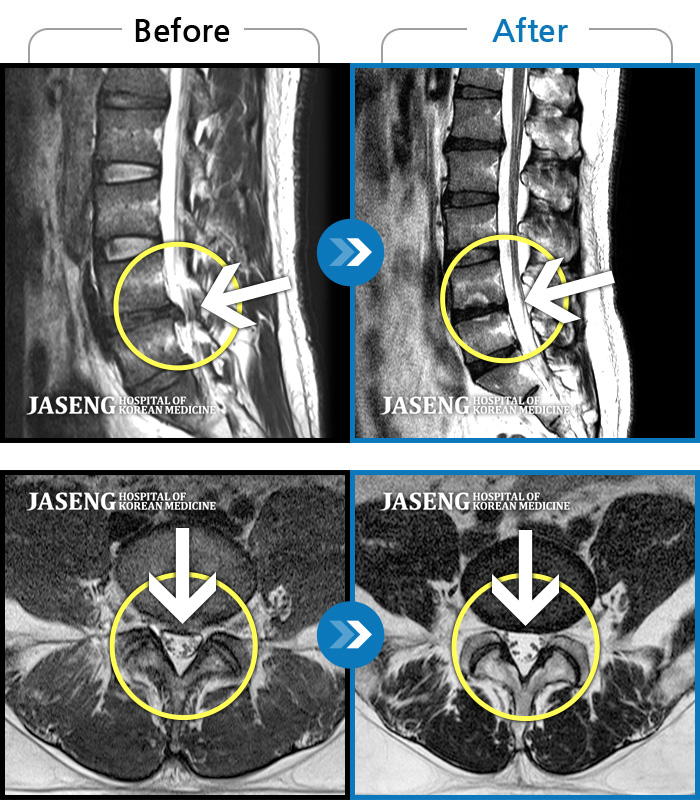

MRI 치료사례

좌측 허리통증, 골반, 종아리 및 발목, 발등 부위의 찌릿한 통증으로 일상 생활에 심한 지장을 초래